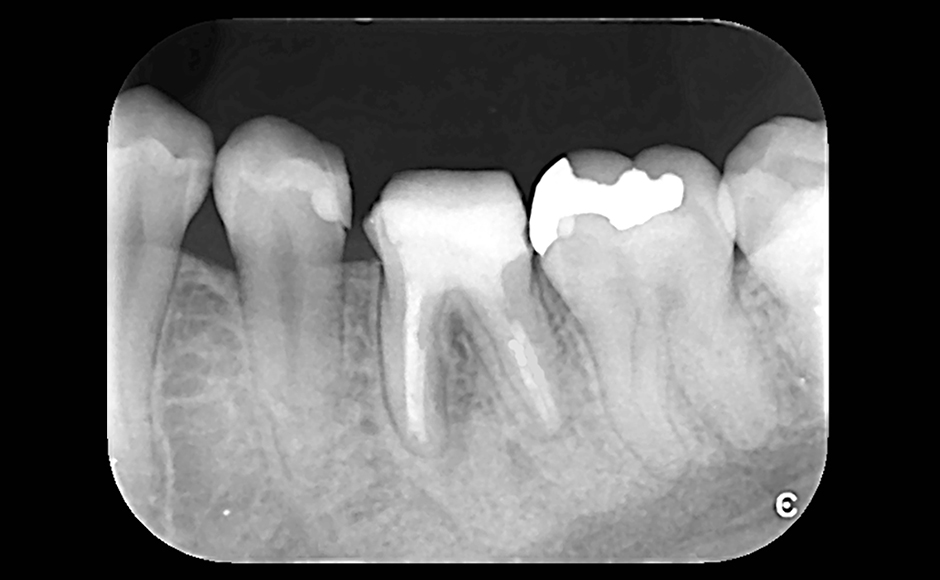

歯の長期保存を目指す根管治療

症例1:頰側および口蓋側に瘻孔を認める根尖性歯周炎に対してレーザーを併用して根管治療を行った症例

症例2:消失しない瘻孔に対し、レーザーを併用した非外科的歯内療法にて根尖性歯周炎の治療を行った症例